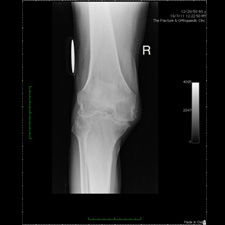

Patient seen with Bilateral Knee Pain and had been unable to walk for two (2) years.

On clinical and radiological examination, he was assessed as having Severe Primary Osteoarthritis of both knees.